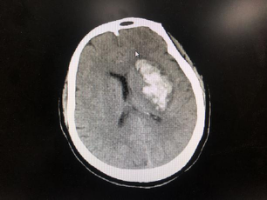

患者头颅CT示可见左侧基底节区团块状高密度出血灶,左侧侧脑室受压变窄。